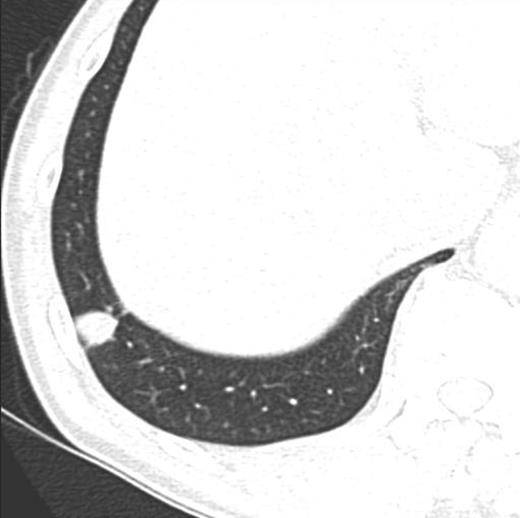

A 59-year-old Japanese man visited our hospital in April 2013 for a workplace medical examination. He was a former smoker (from 20 to 26-year-old, 1 pack per day), and had neither physical symptoms nor family history of malignancies. The chest X-ray did not detect an abnormal shadow, but a CT showed a mass with an irregular margin measuring 18 × 15 mm in diameter at the subpleural area of S9 of the right lower lobe (Fig. 1). The CT detected no nodules in the other lobes or regional lymph nodes swelling. A FDG-PET was performed, but did not yield a definitive FDG accumulation (data not shown). Such tumor markers as CEA, SLX, SCC, CYFRA, NSE, and ProGRP were all within their normal ranges. In May 2013, a lung partial resection was performed under video-assisted thoracic surgery (VATS). At the time of thoracotomy, the mass located at the periphery of S9 of the right lower lobe and the surface was whitely transparent (Fig. 2A). The mass was solid and hard on palpation (Fig. 2B). The intra-operative pathological findings (frozen section) revealed inflammatory granuloma with coagulation necrosis. The permanent pathological examination showed occlusion of the peripheral pulmonary artery by worms and formation of a necrotic mass surrounded by reactive inflammatory cells and hemorrhage in hematoxylin–eosin stain (Fig. 3A) and Elastica van Gieson stain (Fig. 3B). Post-operative course was uneventful, and he is doing well 15 months after surgery.

Pre-operative chest CT scan demonstrated the mass measuring 18 × 15 mm with spiculation at the periphery of S9 of the right lower lobe.